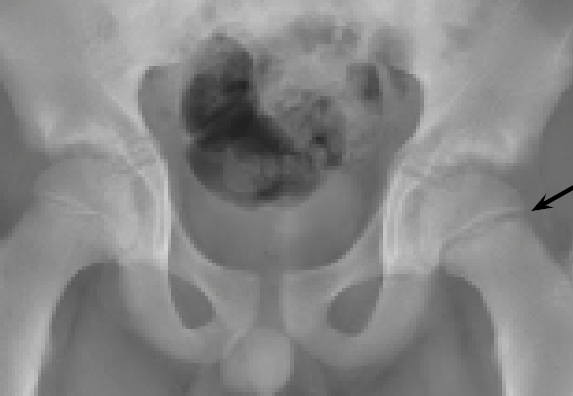

Why Does This Preteen Have Hip Pain?

A 12-year-old boy presented to the orthopedic clinic with left hip pain that began after he was tackled at a school football game.